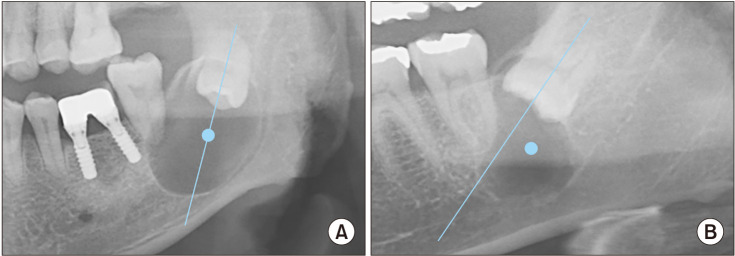

Objectives: This study identifies factors for differential diagnosis among lesions by retrospectively comparing panoramic and cone-beam computed tomography images and analyzing the characteristics of lesions associated with impacted mandibular third molars (IMTs).

Materials and methods: A retrospective cohort study was conducted in patients who simultaneously underwent IMT extraction surgery and related benign tumor resection or cyst enucleation at our institution from 2017 to 2021. To compare the characteristics of each group, two comparative analyses were conducted. The first comparison considered the most frequently observed lesions associated with IMTs: dentigerous cysts, odontogenic keratocysts (OKCs), and ameloblastoma. The second comparison involved placing dentigerous cysts, which have a relatively low recurrence rate, into group A and placing OKC, ameloblastoma, and odontogenic myxoma, which have high recurrence rates, into group B.

Results: Significant differences in the size of the lesion were found in the order of ameloblastoma, OKC, and dentigerous cyst (P <0.05). The buccolingual width of ameloblastoma differed significantly from that of the other groups, with no significant difference observed between the OKCs and dentigerous cysts (P=0.083).

Conclusion: Patient age and lesion size differed significantly among lesion types associated with IMTs, with younger age and larger lesions for OKCs and odontogenic tumors. OKCs are likely to have a larger mesiodistal width than dentigerous cysts. The buccolingual width of ameloblastomas was larger than those of dentigerous cysts and OKCs.